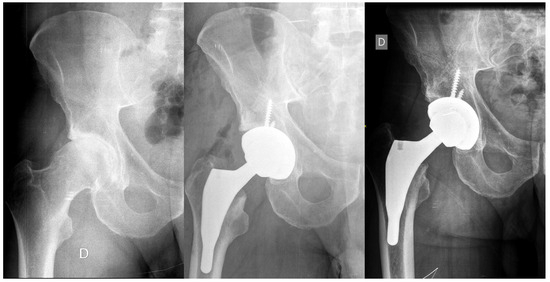

Total Hip Replacement with a Fully Hydroxyapatite-Coated Shortened Stem: Five- to Thirteen-Year Follow-Up Results

2.2. Implants